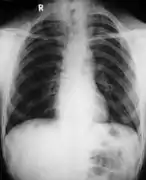

Poor development of the clavicles and a bell-shaped rib cage in a person with CCD

- Clavicles (collarbones) can be partly missing leaving only the medial part of the bone. In 10% of cases, they are completely missing.[10] If the collarbones are completely missing or reduced to small vestiges, this allows hypermobility of the shoulders including ability to touch the shoulders together in front of the chest.[11] The defect is bilateral 80% of the time.[12] Partial collarbones may cause nerve damage symptoms and therefore have to be removed by surgery.